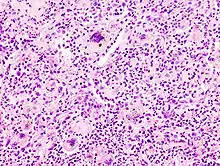

Foreign-body giant cell reaction to a suture. H&E stain.

Micrograph showing a foreign body engulfed by a giant cell. H&E stain.

Foreign body giant cell reaction to silicone leakage from breast implant. H&E stain.